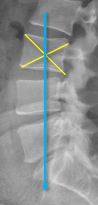

Q what is the name of this measurement? and what is the average + range?

A: Cobb's Method/ Cobb-Lippman method

assesses the degree of a spinal curvature (scoliosis). No average or range is specified as it is used to measure a pathology.